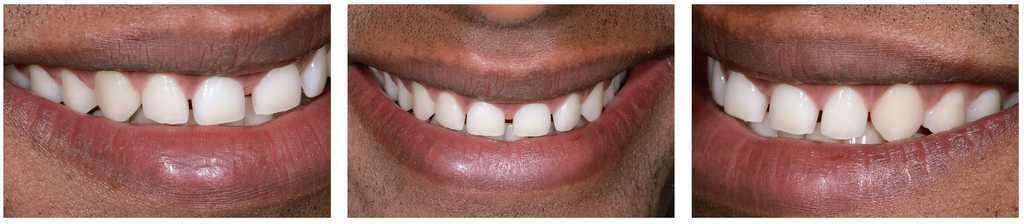

Figs. 2a a 2c. La situación antes de la operación presenta deficiencias en las proporciones de anchura y longitud de los incisivos centrales superiores, diastemas y una ligera sonrisa gingival.

Figs. 4a a 4c. Las imágenes de detalle de los dientes anteriores superiores muestran una erupción incompleta de los incisivos.

Figs. 9a a 9c. La situación 90 días después de la intervención quirúrgica y un blanqueamiento de dos semanas en casa. El recorrido gingival sigue la línea labial inferior y ya no se aprecia sonrisa gingival

Figs. 10a y 10b. El nuevo recorrido gingival.